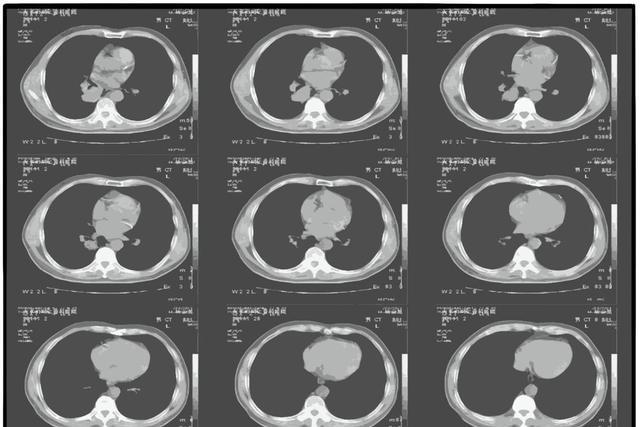

第三个:报告出现"纵隔或肺门淋巴结肿大",或者"伴阻塞性肺炎、肺不张"

这两类描述比前两种更需要重视,原因在于它们说明的不仅仅是结节本身的问题,而是病变对周围结构已经产生了影响。

肺门和纵隔是肺部的"核心地带",淋巴结分布密集,参与免疫应答。感染或炎症确实可以引起淋巴结短暂肿大,消炎后恢复,这属于正常范畴。

但如果淋巴结肿大明显、多发、结构紊乱,且伴随其他异常,需要警惕肿瘤转移的可能性。肺癌一旦出现淋巴结转移,分期已不再是早期,治疗选择和预后都会受到直接影响。

阻塞性肺炎和肺不张是另一个角度的警示信号。二者出现的根本原因,通常是气道某处发生了堵塞,气体无法正常通过,导致远端肺组织出现炎症或萎缩。堵塞物可能是肿瘤,也可能是异物,不管哪种情况,都需要进一步支气管镜或增强CT来明确原因。

有一种情况要特别留意,就是某个肺叶的肺炎反复发作,治疗后好转,过段时间又出现在同一个位置,这种"固定性肺炎"背后很可能有支气管腔内病变,不能一次次当普通感冒处理就算了。